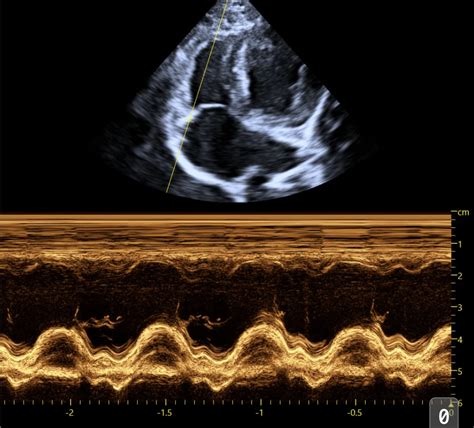

Alright, let’s start with the parasternal long-axis view , often called the PLAX. This is probably the most fundamental view you’ll learn. We get this by placing the ultrasound probe on the chest wall, typically to the left of the sternum, between the ribs. The name itself gives us clues: ‘parasternal’ means next to the sternum (breastbone), ‘long-axis’ means we’re looking at the heart lengthwise, from the base (where the great vessels exit) towards the apex (the pointy tip). In this view, you guys will see the left ventricle (LV) , the left atrium (LA) , the aortic outflow tract , and the mitral valve . We can assess the size of the LV, its wall thickness, and how it’s contracting. We can also get a good look at the mitral valve’s function and the aortic valve. This view is absolutely critical for assessing systolic function (how well the heart pumps blood out) and diastolic function (how well it relaxes and fills). We often use it to measure things like ejection fraction and fractional shortening, which are key indicators of the heart’s pumping efficiency. It’s like getting a side-profile picture of the heart’s main pumping chamber and its exit route. You can also visualize the interventricular septum and the posterior wall of the left ventricle, comparing their thickness and motion. It’s a fantastic starting point for identifying chamber enlargement, hypertrophy (thickening of the heart muscle), or dilation (enlargement). Don’t underestimate the power of this single view; it provides a wealth of information for initial cardiac assessments. We often begin our systematic scan with the PLAX, orienting ourselves before moving on to more specialized views. It sets the stage for understanding the overall cardiac architecture and function.